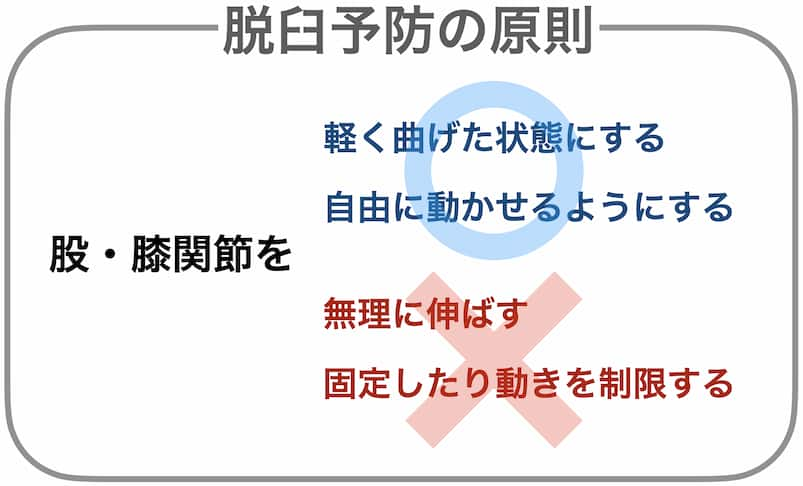

脱臼しない育て方

出生直後の股関節は、臼蓋が浅くて不安定な状態です。その後、骨頭が臼蓋の中で自由に動くことで、臼蓋が深くなり脱臼しない股関節に成長します。上手に臼蓋を育てるためには、股・膝関節を軽く曲げた状態で自由に動かせるようにすること、そして無理に関節を伸ばしたり、固定して動きを制限しないことが大切です。特に出生直後〜2ヶ月までが重要だといわれています。